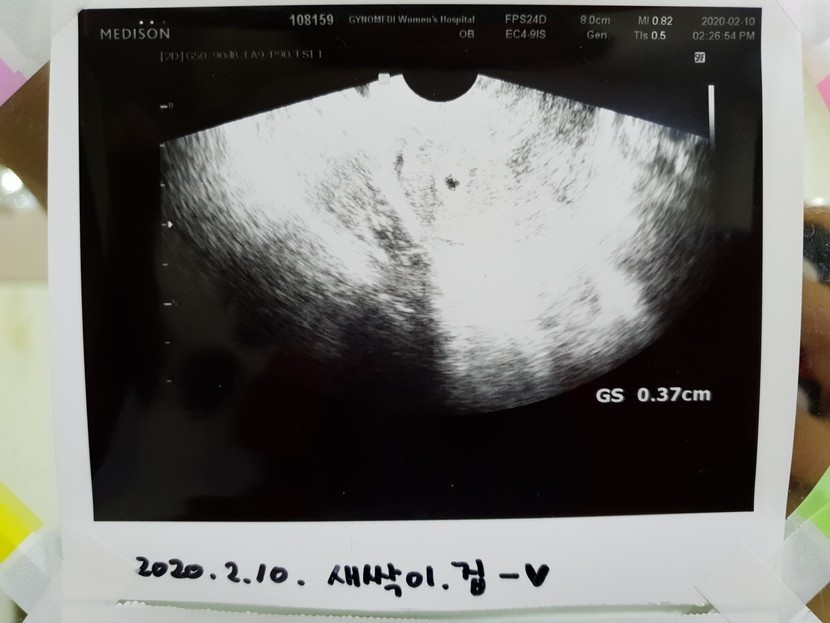

병원가니 피수치를재고396 입신입니다.

일주일뒤에 오래서 갔더니

예전에는 심장뛰는거 봐야 임신확인서를 주는데

요새는 아기집만 초음파로 보일시

임신확인서를 끈어주네요ㅎㅎ